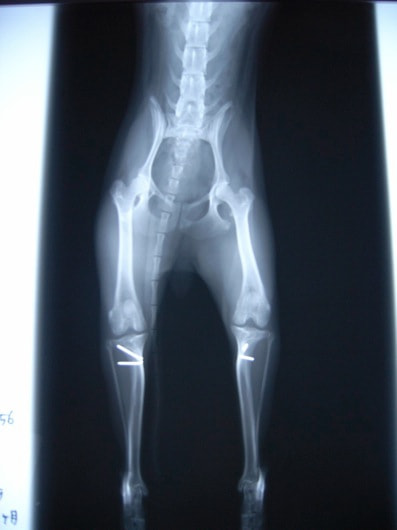

■ 症例20 ポメラニアン 8ヶ月 1.8kg

左右膝蓋骨脱臼 グレードⅢ

2ヶ月前から間欠的跛行が認められ、両膝の膝蓋骨脱臼整復術を行った。

手技は縫工筋及び内側広筋の解放、脛骨粗面の外側転位、滑車ブロック形造溝術、内外側関節包の縫縮を選択し実施した。

右側の膝蓋骨脱臼は上記手技で整復されたものの、左側はそれのみでは膝蓋骨が浮く様子が認められた。その為、PDS縫合糸にて膝蓋靱帯を1糸のみ縫合し、靱帯の縫縮を行った。

膝蓋骨脱臼は膝関節における膝蓋骨の内外側の脱臼と定義されるが、時として単純な内外の脱臼ではなく、膝蓋骨が大きく前方に浮き上がるように脱臼する場合がある。特にトイプードルやポメラニアンといった犬種に多く認められる。

内側脱臼に加えて前方への浮き上がりを矯正する為に、従来より脛骨粗面転移により膝蓋靭帯を外方と下方に引っ張り、固定する方法を選択する。膝蓋骨の前方への浮き上がりが軽度の場合は、従来法ではなく関節包の縫縮で対応していた。しかし、一部の症例で膝蓋骨の動きが悪くなり伸展機構が円滑に機能せずロボット様歩行になるケースがあった。

その為、膝蓋靭帯自体を縫縮する方法を採用した。この方法により、膝関節の伸展機構を妨げず膝蓋骨の軽度の浮きを矯正することが可能となった。

本症例の経過は良好である